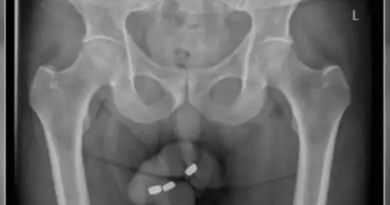

Foto: Reprodução | A paciente viajou para regiões onde os parasitas são endêmicos. Segundo o estudo, ela consumiu alimentos crus, como sushi e salada.

A paciente viajou para regiões onde os parasitas são endêmicos. Segundo o estudo, ela consumiu alimentos crus, como sushi e salada. Os médicos fizeram uma punção lombar e a diagnosticaram com meningite eosinofílica. A causa mais comum de meningite eosinofílica é a angiostrongilíase, que é causada pelo Angiostrongylus cantonensis.